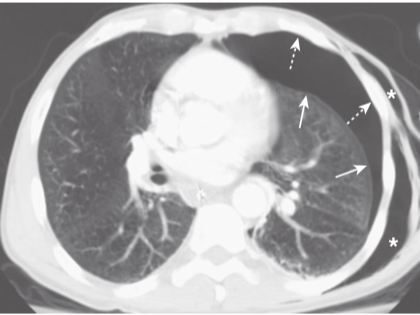

Pneumothorax seen on CT.

As the lung collapses, it tends to maintain its usual shape so that the curve of the visceral pleural line (solid white arrows)parallels the curve of the chest wall (dotted white arrows). This is important in differentiating a pneumothorax from artifacts or other diseases that can mimic a pneumothorax. As it collapses, the lung on the side of the pneumothorax also tends to remain lucent until the lung loses almost all of its normal volume, at which point it becomes more opaque. This patient also has subcutaneous emphysema–air in the soft tissues–of the left lateral chest wall (white stars). The patient had been stabbed by a friend.